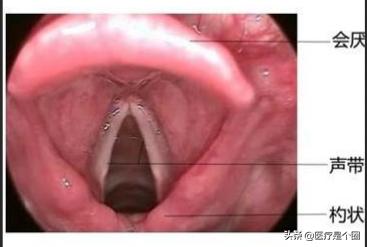

声带是发声器官的主要组成部分。位于喉腔中部,由声带肌、声带韧带和粘膜三部分组成,左右对称。声带的固有膜是致密结缔组织,在皱襞的边缘有强韧的弹性纤维和横纹肌,弹性大。两声带间的矢状裂隙为声门裂。

声带是人类发声的主要结构,从极轻微的声嘶到完全失声,多为声带病变或其他病因使声带的正常运动发生障碍所致。声带位于喉腔假声带(室带)下方,左右各一,由声韧带、肌肉和黏膜组成,前起甲状软骨板交角内面,后端止于勺状软骨底部前端的声带突。声带张开时,出现一个等腰三角形的裂隙,称为声门裂,空气由此进出,亦为喉部最窄处。

声门示意图

说那么多,就是喉咙那两块纵行的“肉”,这个肉的长度、宽度、松紧度的不同形成了大人、儿童、男人、女人声调高低的不同,青少年时期,所面临的变声就是这个地方出现的变化。